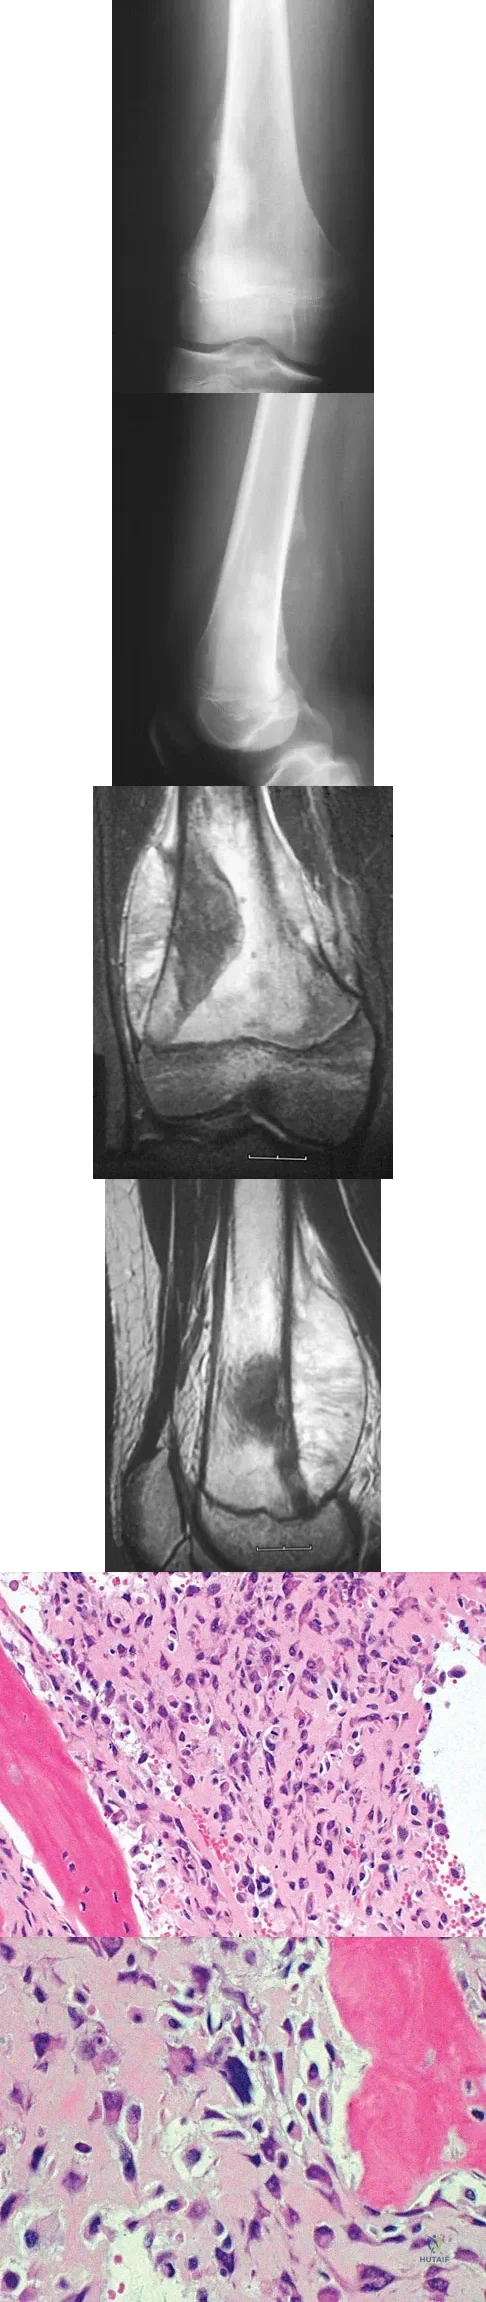

A 13-year-old boy has knee pain after sustaining a mild twisting injury while playing basketball 4 weeks ago. Radiographs and MRI scans are shown in Figures 24a through 24d, and biopsy specimens are shown in Figures 24e and 24f. Treatment should consist of

Explanation